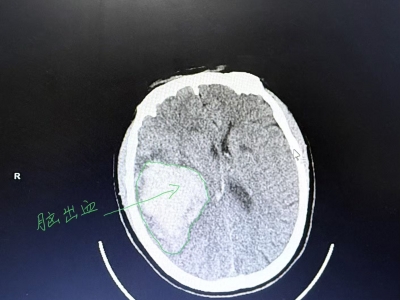

【无影灯下】一次手术 拆除两颗颅内“炸弹”